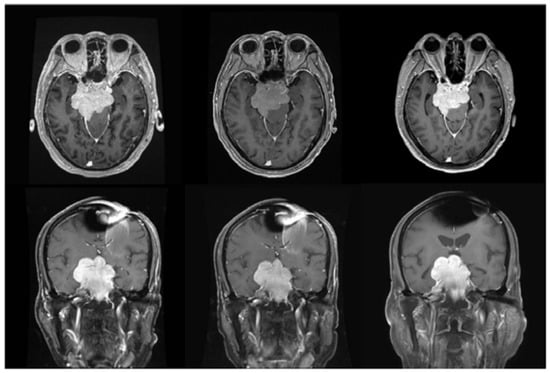

2.3. Case 197

| 197 | 11 February 2022 | 1428 | 40.84 | 17.62 | 13.00 | CR | 20 December 2022, CR | 10 |

| 197 | 59/Female | Atypical meningioma | Right high frontal | 2.64 | RT + OP + ChemoT |